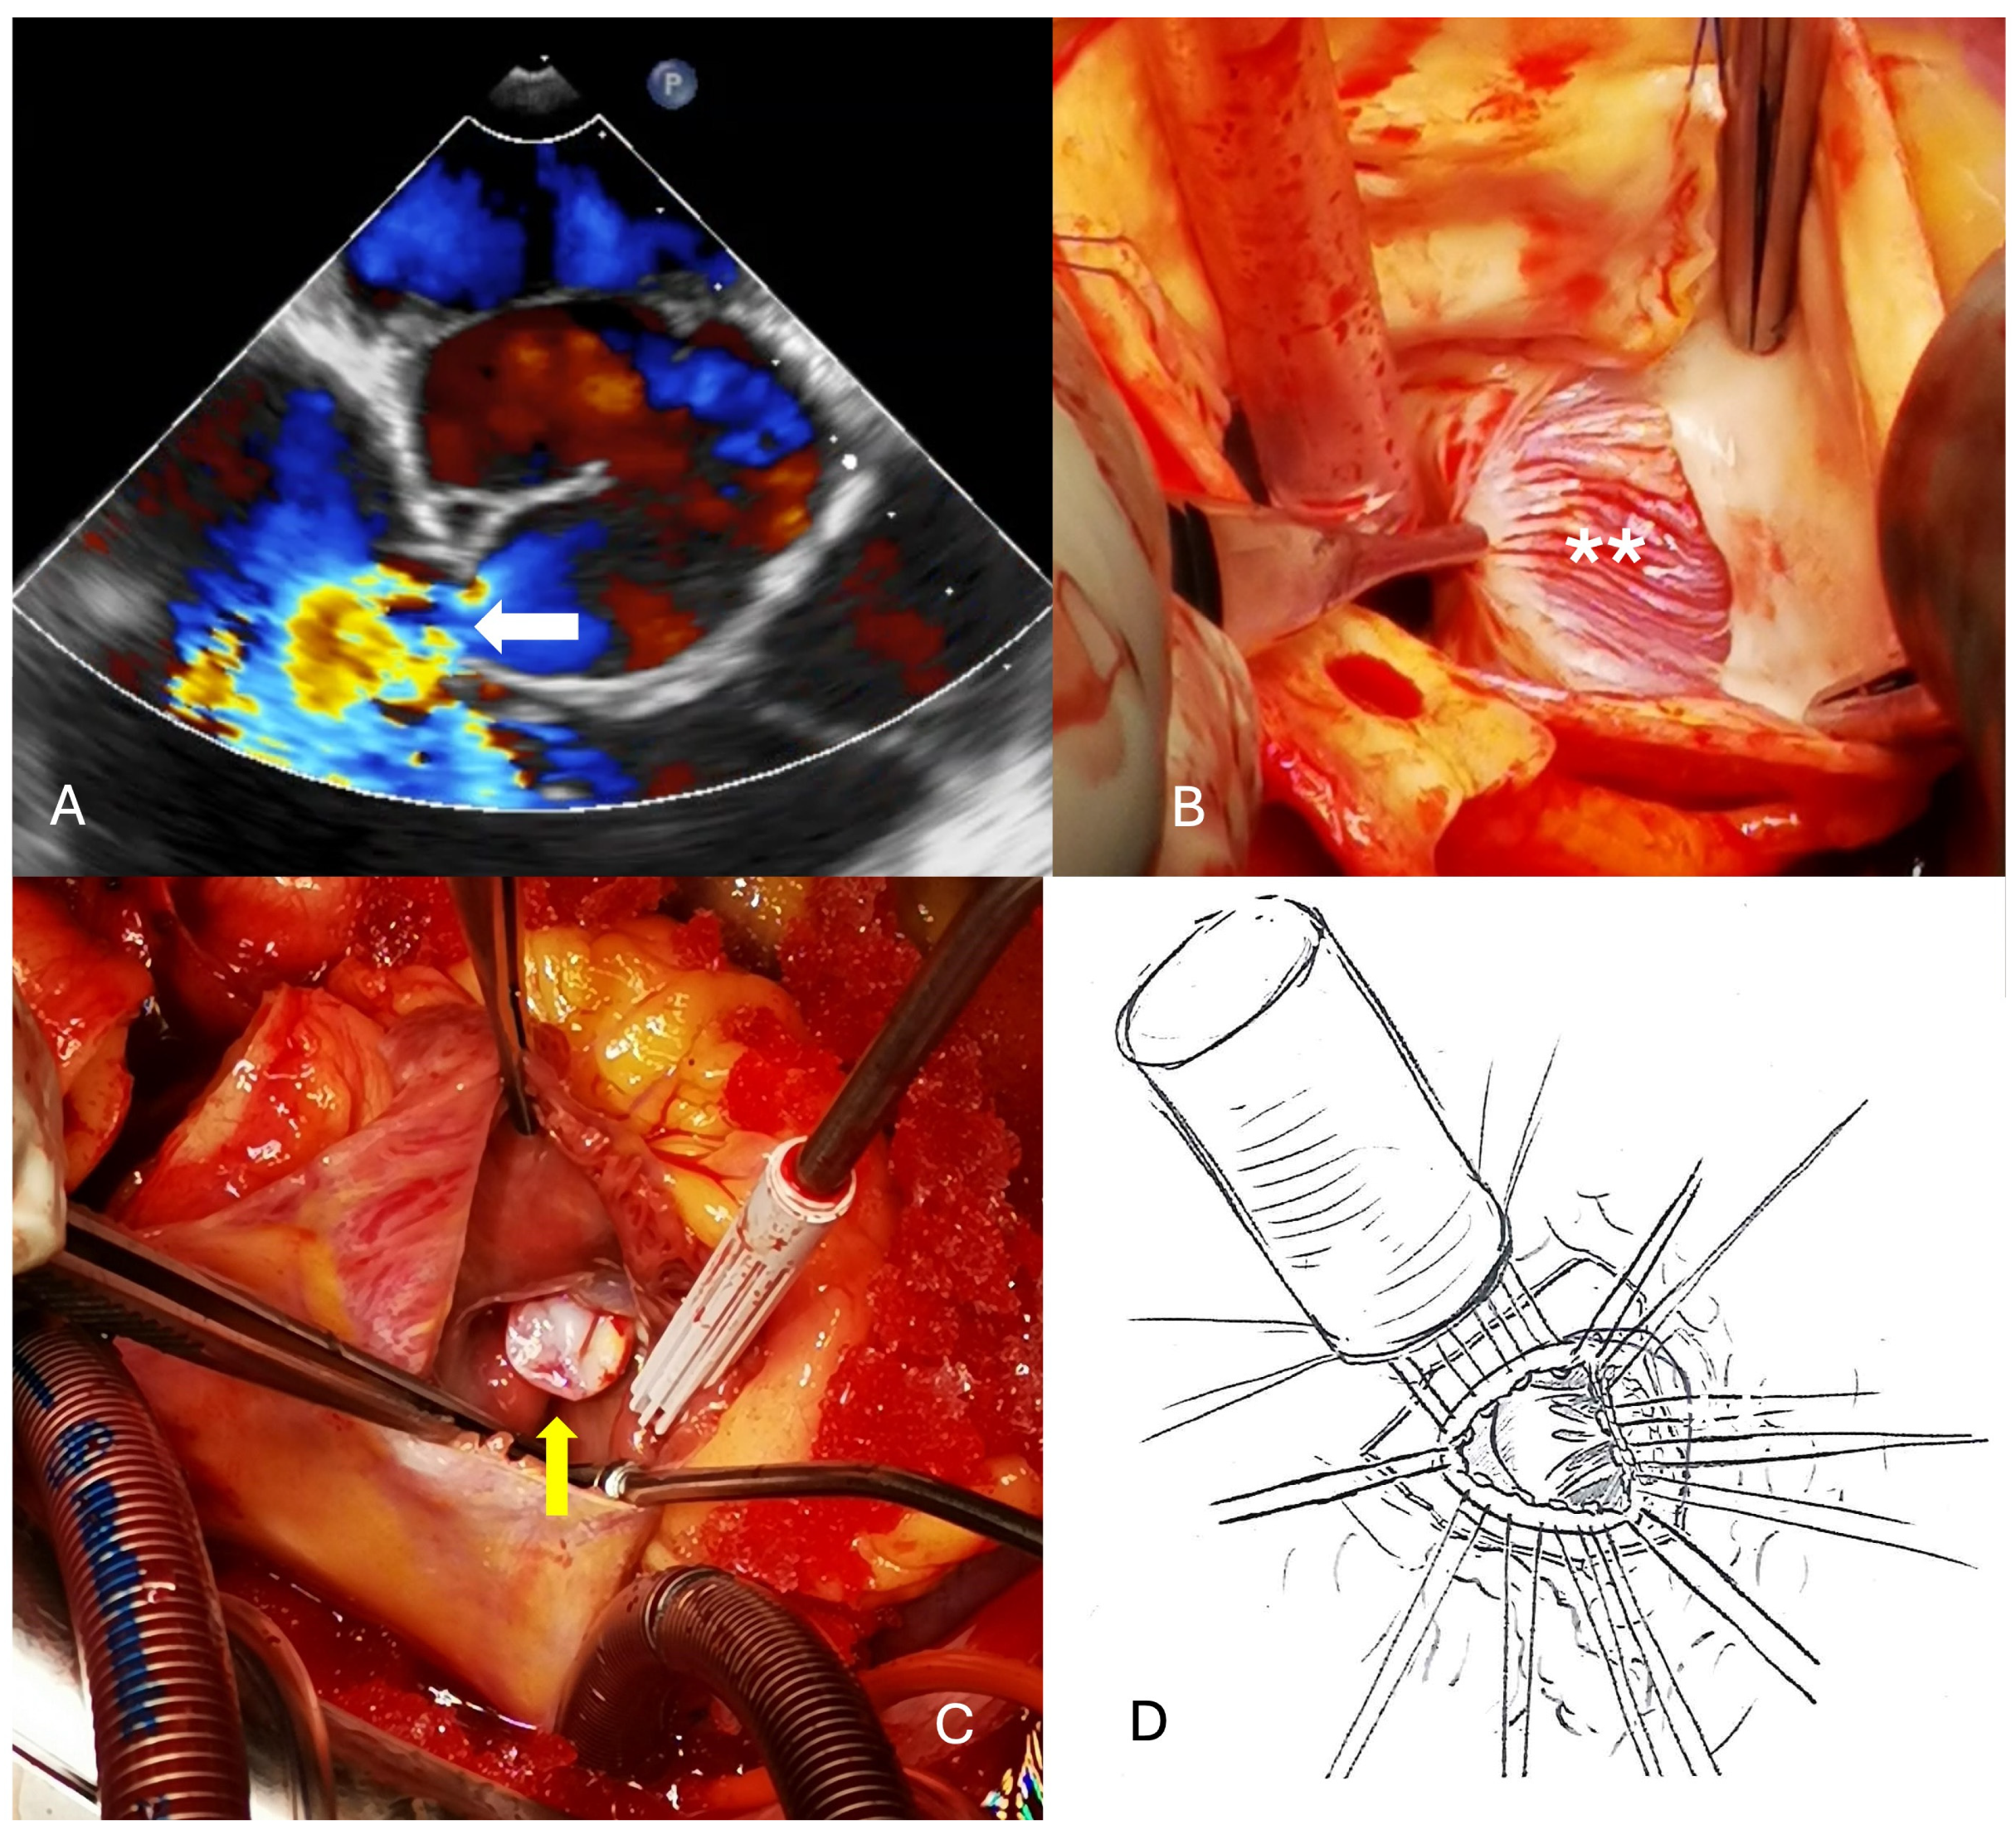

The fourth case was a 41-year-old man who presented with palpitations and unspecific chest pain occurring during exercise but at rest as well. ECG showed sinus tachycardia and echocardiography revealed a 5.3 cm SVA of the right sinus protruding into the right ventricle but also into the septum with a moderate narrowing of the left ventricular outflow tract. A CT scan showed no coronary calcifications. The large defect was localized on the left side of the right coronary ostium and closed with a large xeno-pericardial patch from inside the aortic root. Postoperative outcome was excellent, but on first CT scan, there was still a little bit of contrast entering the aneurysmal sack. Six months later, the aneurysm had completely thrombosed and narrowed to a size of about 2 cm (Figure 4).

Figure 4. (A) Large aneurysm of the right sinus of valsalva with compression of the left ventricular outflow tract (white *). (B) Closure with a large patch (white arrow) to exclude the aneurysm (resection not possible). (C) Intraoperative transesophageal echocardiography showing normal flow condition in the left ventricular outflow and aortic root without turbulences into the former aneurysm cavity. (D) Before closing the chest, the aneurysm cavity had already thrombosed (white **).